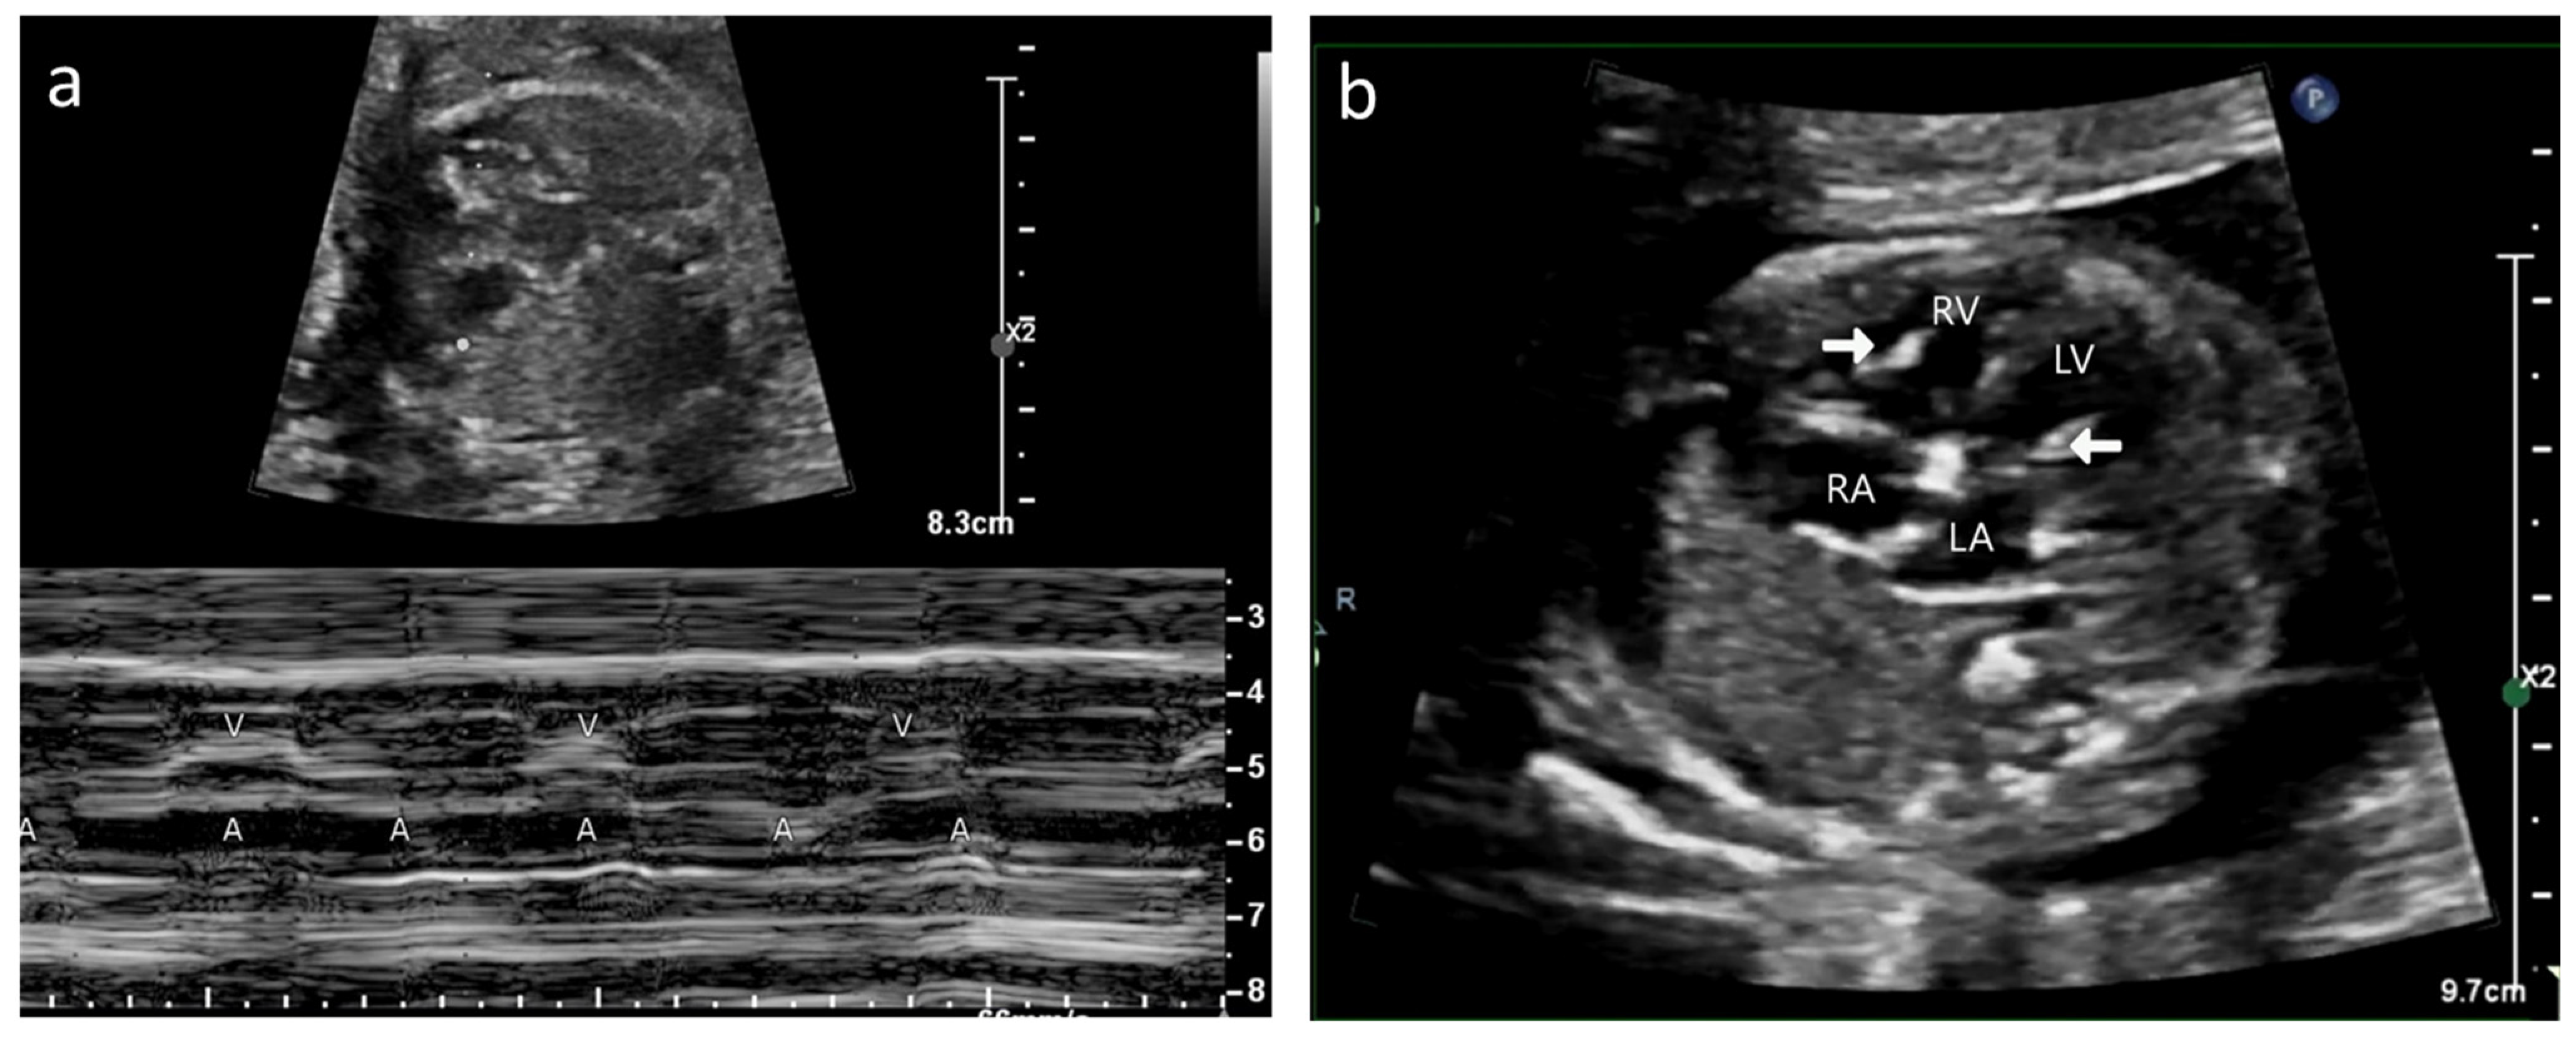

2.1.1. Case A

2.1.2. Case B

5.5. Echocardiography Correlation